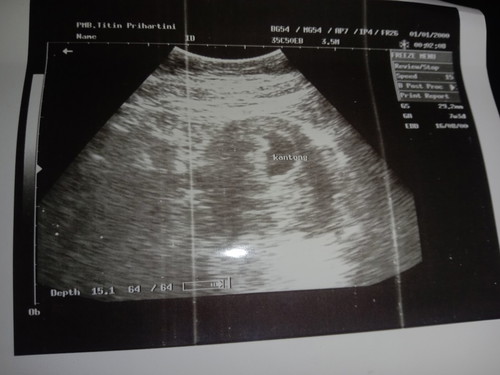

hasil usg

Usia kandungan 7w3d .. janin belum terlihat wajar atau TDK ..mohon bantuan jawabananya

Wajar kalo bunda usg perut 2D bun, Usia kehamilan dibawah 8w memang kadang ada yg sudah klhtn dedenya ada yg cumn kantong aja karna ketebalan perut beda beda & kondisi kandung kemih saat USG lagi penuh atau kosong juga mempengaruhi, jd gk usah kefikiran ya bunda, insyallah dede sehat kok😊 biasanya usia 4-7w lebih jelas keliatan kalo pakai USG transvaginal,

Wajar bunda, aku pun waktu 6w masih kantong, kalahpun 7w3d blm terlihat mungkin masih sngt kecil, saya pun skrg jln 9minggu perut kadang ada getaran. Tapi blm usg lagi krna mau menunggu 12w saja biar gk keseringan usg kalau masih TM1, kecuali mendekati kelahiran baru sering usg.

Wajar bun. Masih embrio klo kelihatan juga cm kayak kacang kecil bgt. Tapi kebanyakan cm kelihatan penebalan kantung rahim aja. Nanti USG lagi pas 12 w biasanya udah lengkap organ luarnya